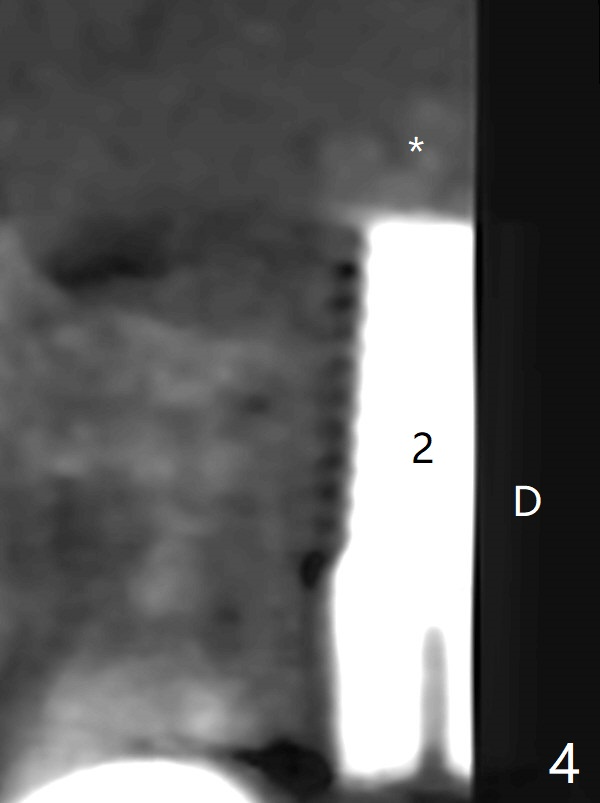

After osteotomy using bone-level implant guide at #4, the crown and abutment at #3 has to be removed to place a 4x14 mm tissue-level dummy implant because of the narrow space of #4 and implant placement angulation (Fig.1). Following initial placement of a final 4x17 mm implant and bone graft (Fig.2 *), the crown and abutment of #3 and the guide are reseated for correct implant trajectory. The guide has to be removed for final depth control. With the same mode, a 5x17 mm tissue-level tap is used at #2 following bone-level osteotomy with guide. A 5x14 mm tissue-level implant is placed with >50 Ncm (later placed deeper), while more bone graft is inserted mesial of #4 implant with a 3.5x5 mm abutment (Fig.3 *). Bone graft is introduced into the sinus using guided sinus lift kit (Fig.4,5 (CT sagittal and coronal sections)) * (D: distal, P: palatal)). The coronal half of the implant at #4 is covered by bone graft (Fig.6 *) buccal (B) and palatal within the deep socket. The implants at #2 and 4 seem to have osteointegrated nearly 5.5 months postop (Fig.7,8 (BW)). A 4.5x5 mm unipost is later placed at #2 with long chamfer margin. It appears that the abutment at #3 is wide. The hex is worn. It changes to a 5.5x7(4) mm one. After abutment adjustment for parallelism, a provisional FPD is fabricated. The latter will be adjusted for papilla formation between implants to reduce food impaction.